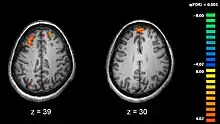

Données neurophysiologiques obtenues par imagerie cérébrale

Avec le développement récent des techniques d'imagerie médicale, beaucoup de travaux sont consacrés à l'étude de différences structurelles ou fonctionnelles dans certaines régions cérébrales chez des personnes schizophrènes par rapport aux individus non schizophrènes.

Le cerveau des personnes avec schizophrénie serait d'apparence globalement normale et seules des techniques récentes d'imagerie cérébrale, utilisées lors d'étude sur des cohortes de patients, ont pu mettre en évidence certaines différences. La première différence structurelle observée fut la découverte d'un élargissement des ventricules cérébraux chez des patients dont les symptômes négatifs étaient particulièrement marqués[159]. Toutefois, ce résultat ne s'avère guère utilisable au niveau individuel, du fait de la grande variabilité observée entre les patients. Un lien entre l'élargissement ventriculaire et une exposition aux médicaments neuroleptiques a cependant été suggéré[160]. Des études plus récentes ont par la suite montré qu'il existe de nombreuses différences dans la structure cérébrale selon que les personnes présentent ou non un diagnostic de schizophrénie[161]. Toutefois, comme dans le cas des études antérieures, la plupart de ces différences ne sont détectables que lorsque des groupes, et non des individus, sont comparés, et ne sont conséquemment pas utilisables pour établir le diagnostic de schizophrénie.

Des études mettant en œuvre des tests neuropsychologiques combinés à des techniques d'imagerie cérébrale comme l'imagerie par résonance magnétique fonctionnelle (IRMf) ou la tomographie par émission de positons (TEP) ont cherché à mettre en évidence des différences fonctionnelles d'activité cérébrale chez des patients. Elles ont montré que ces différences surviennent plus fréquemment au niveau des lobes frontaux, de l'hippocampe et des lobes temporaux[162]. Ces différences sont fortement liées aux déficits cognitifs fréquemment associés à la schizophrénie, notamment dans le domaine de la mémoire, de l'attention, de la résolution de problèmes, des fonctions exécutives et de la cognition sociale.